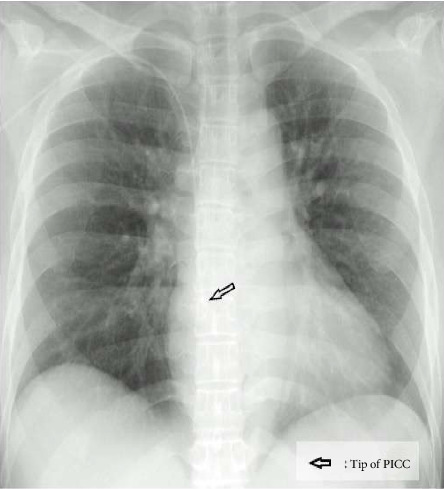

背景:一名全麻患者体位改变后发生暂时性心律失常的新病例报告强调了由于患者体位改变时外周插入的中心静脉导管([CVC] PICC)尖端尾侧运动可能导致潜在致命性心律失常的可能性。病例介绍:我们报告了一个44岁的女性患者在全身麻醉下进行腹腔镜肾上腺切除术,在体位改变后发生的暂时性心律失常。患者术前使用心电图(ECG)引导的针尖确认系统(TCS)插入PICC。结论:本病例报告讨论了全麻下最佳TCS,强调警惕心电监测,提出了预防全麻下心律失常的措施。

Background: The novel case report of a temporary arrhythmia that developed after a positional change in a patient under general anesthesia emphasizes the possibility of potentially lethal cardiac arrhythmias that may develop owing to caudal movement of the peripherally inserted central venous catheter ([CVC] PICC) tip when changing patient positions. Case Presentation: We present a case of temporary arrhythmia that developed after a positional change in a 44-year-old female patient scheduled for laparoscopic adrenalectomy under general anesthesia. She had undergone preoperative insertion of a PICC using an electrocardiogram (ECG)-guided tip confirmation system (TCS). Conclusion: The case report discusses the optimal TCS and emphasizes vigilant ECG monitoring, suggesting measures to prevent these arrhythmias under general anesthesia.